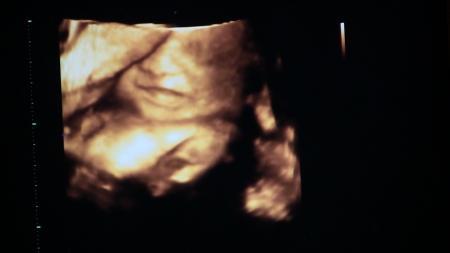

Danke fürs däumchen drücken :) Alles ist super!! Blutdruck ok, Urin ok, Gewicht ok. CTG wurde leider doch nicht gemacht, weil die gestern den letzten tag vorm Urlaub hatten und es sooo voll war, aber da ich ja keine beschwerden hab, sei es auch in ordung, es das nächste mal damit anzufangen. Dann US. Unsere Emily ist putzmunter, liegt mit dem kopf nach unten (hab ich doch richtig gefühlt). Sie ist 37,8 cm groß und wiegt 1280 gramm. Fruchtwasser ist genug da, mumu ist fest und zu. Alles wie es sein soll. Dann hat sie als überraschung ohne ein wort kurz 3D angemacht. (Eigentlich muss ich das ja zahlen) Omg hab ich eine süße Tochter! Ich war sprachlos sie sieht aus wie ich als baby - original. Dann hab ich noch meine zweite anti- D profilaxe bekommen. Jetzt heißt es wieder 4 wochn warten. Hier noch 2 fotos.

Bild zu FA- Bericht von gestern. - Forum für Oktober - Mamis